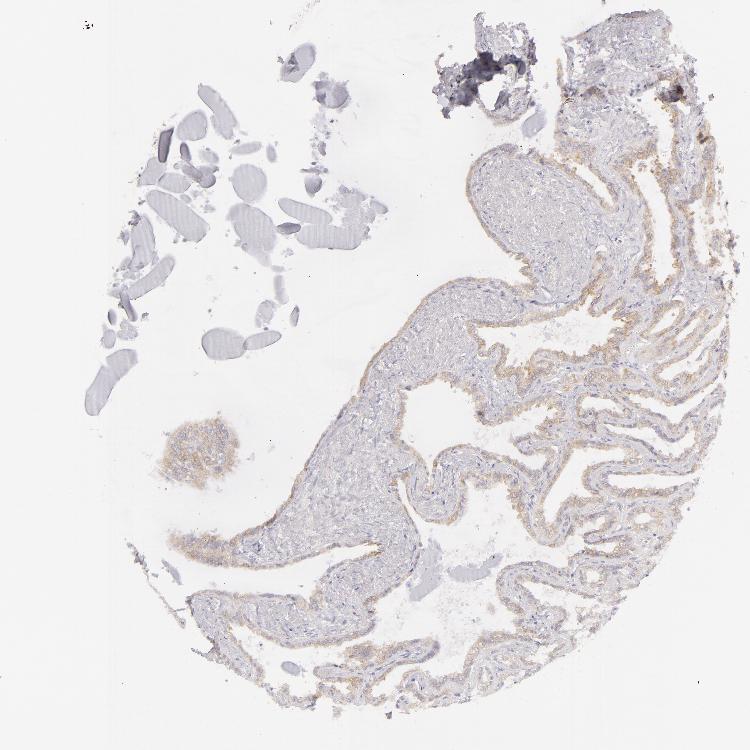

TISSUE PRIMARY DATA SEMINAL VESICLE Show tissue menu

SEMINAL VESICLE - Antibody stainingi

Antibody staining in the annotated cell types in the current human tissue is reported as not detected, low, medium, or high, based on conventional immunohistochemistry profiling in selected tissues. This score is based on the combination of the staining intensity and fraction of stained cells.

Each image is clickable and will lead to virtual microscopy that enables deeper exploration of all samples and also displays staining intensity scores, fraction scores and subcellular localization as well as patient and tissue information for each sample.

Antibody HPA010122Antibody HPA071006Antibody CAB001999Antibody CAB002000

Glandular cells Not detectedNot detectedMediumMedium